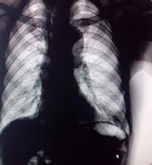

1.X線檢查本病發生於亞段及其以下細小支氣管肺癌,形成腫塊的形態比較複雜。在掌握本病病理和X線征的基礎上,對本病作出正確分型,不僅有利於診斷和鑑別診斷,對臨床治療亦能提供一定指導作用。2.多層螺旋CT檢查多層螺旋是一種較為有效的早期周圍型肺癌臨床檢查和診斷技術,具有較高的臨床套用價值。3.CT靶掃描對早期周圍型肺癌具有較高的診斷價值。